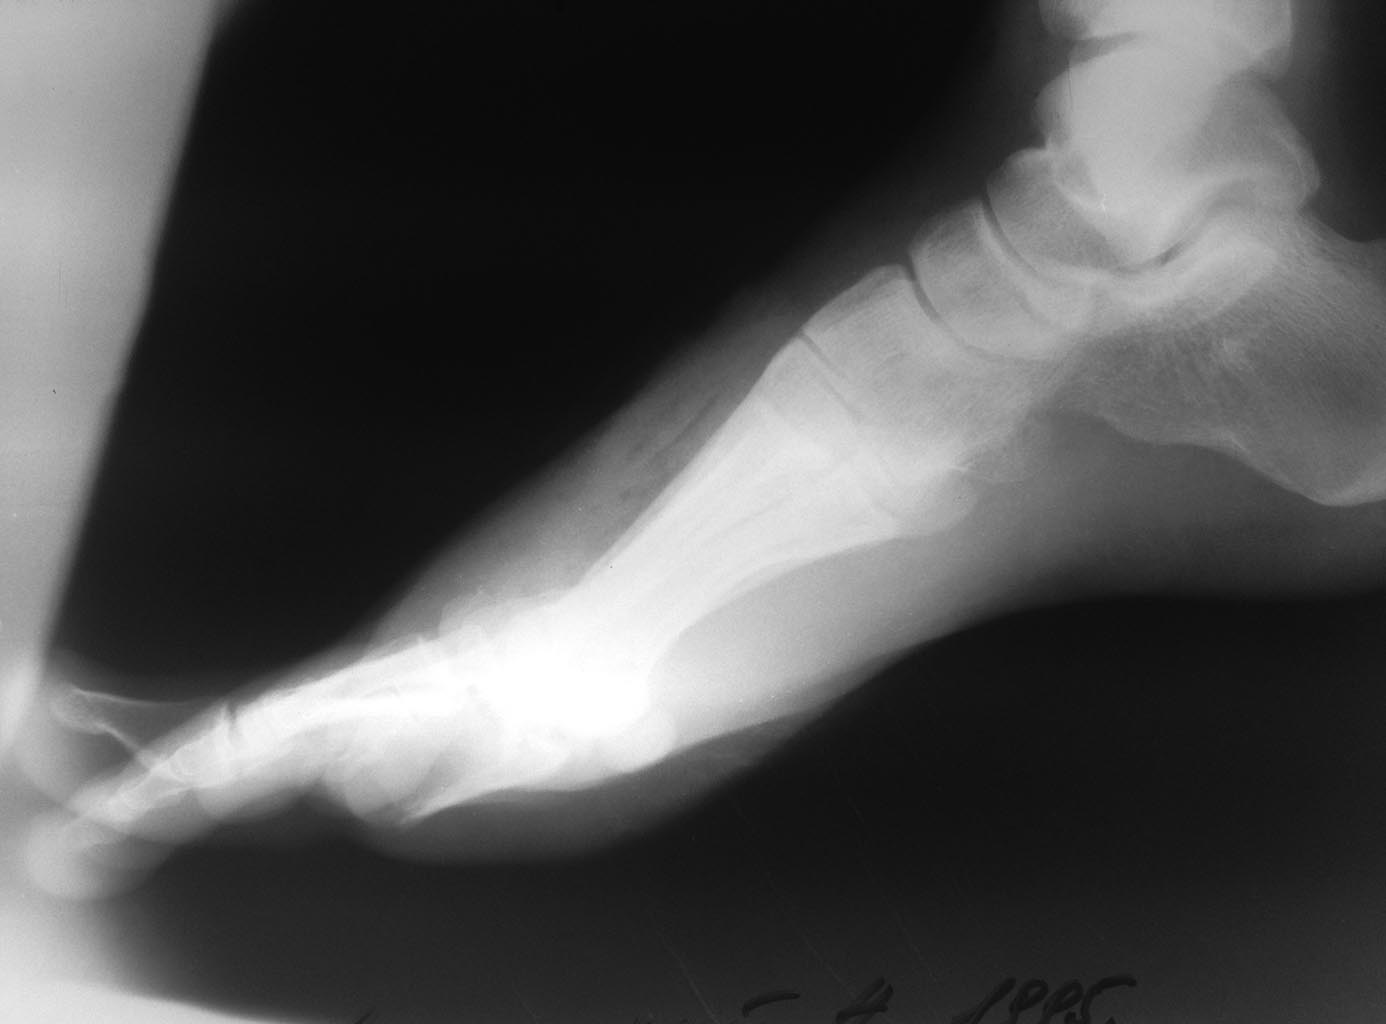

Добрый день!Ситуация неприятная, но не катастрофичная. Лечение потребует несколько этапов. Закрытый остеосинтез головок спицами с подошвенной стороны под контролем ЭОП,I палец потянуть по оси и фиксировать транскутанно спицами 1 мм перпендикулярно плоскости переломов. Сустав скорее всего утрачен, учитывая многофрагментарный характер перелома, но исходно похоже есть плосковальгусная деформация стопы осмотрите внимательно противоположную конечность, сделайте сравнительные снимки, расчертите углы. Вторая проблема заживление мягких тканей отнимет больше времени и сил. Некроз скорее всего будет до сухожилий разгибателей.Вариантов 2 сохранять его как биологическую повязку и уменьшать с периферии - долго, сухожилия все равно оголяться и пластика понадобиться.Либо при явной демаркации некрэктомия, обработка "гидроножем" (есть у Смитов), ВАК и кожная пластика. По сращению переломов и заживлению ран работа с плюснефаланговым суставом. Возможно и не понадобиться.

С уважением Ушаков СА

Здравствуйте. В сложившейся ситуации я бы не заморачивался фиксацией стопы в аппарате или открытой репозицией и фиксацией основной фаланги первого пальца. Все внимание необходимо уделить мягким тканям. По снимкам сложно определить глубину их поражения. Но механизм травмы и то, что мы видим на фотографиях, не дает особых поводов для оптимизма. С целью фиксации пальцев, особенно первого, я бы рекомендовал повязку, обычно накладываемую после реконструктивных операций на переднем отделе стопы. С установкой первого пальца в положение небольшого приведения. Чтобы впоследствии избежать его конфликта со вторым. Такую повязку нужно, по-возможности, менять пореже. И не забывайте о ранней нагрузке на стопу. При хорошей фиксации пальцев повязкой и в послеоперационном ботинке (только без разгрузки переднего отдела, на сплошной подошве) ходьба с нагрузкой до появления болевых ощущений возможна и будет хорошим дополнительным стимулом для заживления, профилактикой регионарного остеопороза и фактором, облегчающим адаптацию к потребующей длительного времени для своего решения проблеме.

А не надо ничего сверхъестественного. Между 1 и 2 пальцами марлевый тампон, костыли, задняя легкая дисциплинирующая лонгетка, гепарин, холод, нпвс. Некроз либо отторгнется корочкой с эпителизацией либо нагноится. Воспринимайте как ожог 3б степени при ведении методом струпа. Недель через 4 нагрузка со стельками с костылями. Срастется раньше, чем заживет.( скорее всего) . И ничего страшного. Терпение...